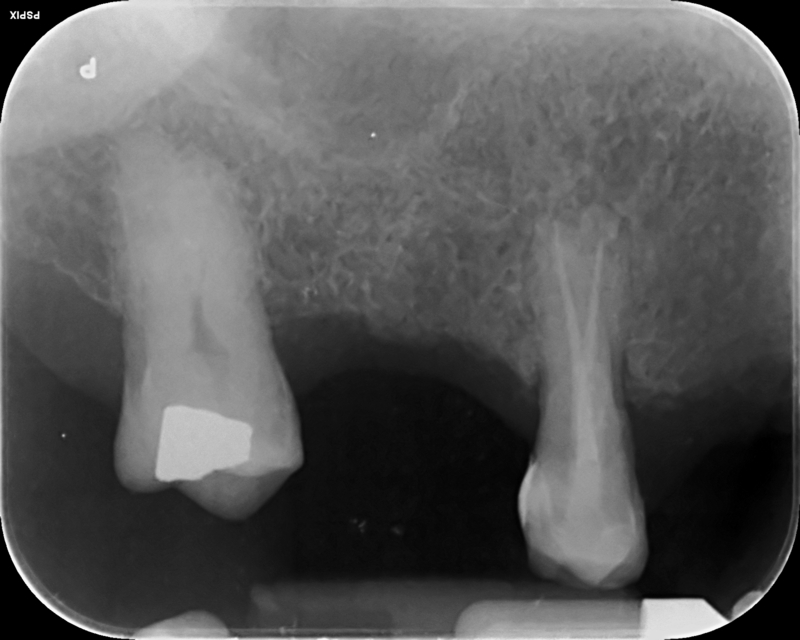

Case 18 – Endodontics

Perforation during root canal treatment and repair